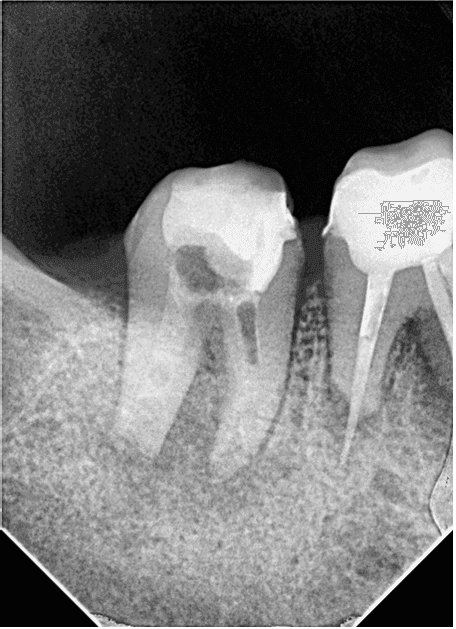

Hastamız 2. Seansa geldiğinde kalsin temizlendi. Apikal bölgedeki taşkın guta 3 boyutlu aktivasyon eğeleri ile çıkarıldı ancak eğeye ulaşılamadı ve kontrol filmi alındı (RESİM 6).

RESİM 6: Kırık eğenin konumu kontrol edildi.